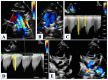

Hypoplastic left heart syndrome is a spectrum of complex congenital cardiac defects. Although in borderline cases, biventricular repair is a viable option, in the majority of cases, univentricular palliation is the treatment of choice. Hybrid palliation can be a valid alternative to classic Norwood operation in the neonatal period, especially in selected cases such as high-risk patients or borderline left ventricles. Echocardiography is the main diagnostic modality in this pediatric population, from the fetal diagnosis to the subsequent surgical steps of palliative treatment. Hybrid palliation is performed after birth and is characterized by surgical banding of the pulmonary arteries along with transcatheter stenting of the ductus arteriosus. There are some peculiar aspects of cardiac imaging that characterize this type of palliation, and that should be considered in the different phases before and after the procedure. We aimed to review the current literature about the role of echocardiography in the management of patients with hypoplastic left heart undergoing hybrid palliation.